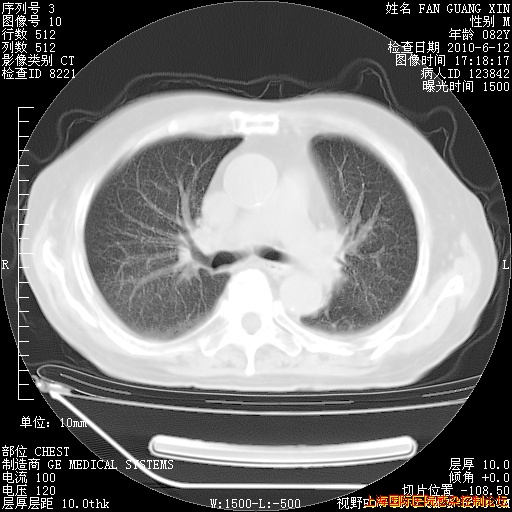

补发6月12日肺部CT肺窗

6月12日肺窗

6月12日纵膈窗

整整相隔30天的肺部CT好像有所好转啊。甲强龙减量第3天,需要观察体温。

海管,自昨日你和我通完话后,不知您岳父消化道症状有无缓解?体温怎样?阅读7.12日胸部ct,个人认为目前激素治疗是有效的,甲强龙减量是适宜的。因在抗痨治疗,需密切观察肝功、肾功能和血常规。不过,老年、长期住院和大量使用激素,很担心菌群失调发生